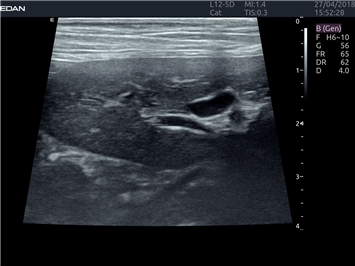

EDAN Acclarix LX4 VET представляет собой профессиональную ультразвуковую систему, специально разработанную для ветеринарных исследований. Сочетание стабильности, высокой производительности и эффективности делает эту систему идеальным выбором для современной ветеринарной практики.

• Оптимизация изображения для различных видов животных

• Улучшенная детализация структур

• Универсальные датчики для различных видов животных

• Специализированные предустановки для ветеринарных исследований